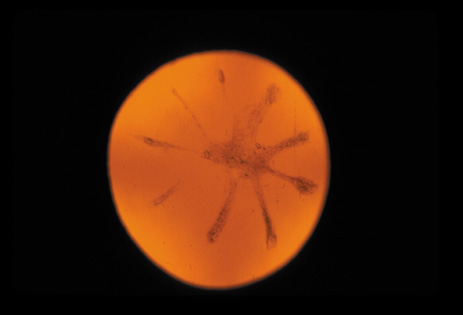

Cortical opacities have been clinically observed to develop earliest in the inferior half of the lens, especially the lower nasal quadrant.28 Epidemiologic29 and laboratory studies30 have suggested that cortical cataracts may be caused by ultraviolet rays from sunlight. The supraorbital margins may block the ultraviolet rays from falling over the upper part of the lens, thus making cortical cataract less frequent in the upper quadrants. Eventually these opacities also develop in the periphery in other quadrants, resulting in a circular array of spokes and peripheral cuneiform opacities (Fig. 9). Bands of central cortical fibers may become prominent and opacify centrally (Fig. 10). However, most cortical cataracts remain in the periphery for many years, even decades, before the central axis of the lens becomes involved, causing loss of vision late in the development of the cataract.

Fig. 9. Moderate cortical changes. Wedge-shaped (cuneiform) or spoke-like (wheel) peripheral changes are seen. These changes may be extensive but may not affect Snellen visual acuity since they occur in the periphery.

This type of cataract is best seen with retroillumination, which gives an enhanced picture of the cortical spokes and vacuoles by the shadows they cast as the light is reflected back by the fundus. Direct illumination helps clarify the level of the opacities (see discussion in the Posterior Subcapsular Cataract section below).